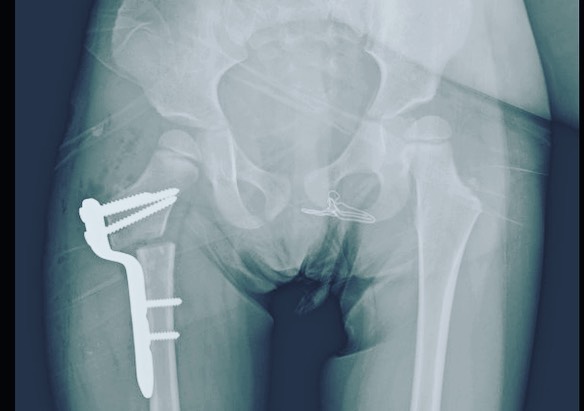

Displasia de cadera

Quiero compartirles que doy de alta a mi pacientita Leilany, de 5 años. La operé por displasia de cadera causada por coxas valgas (región proximal del fémur muy vertical), que alteraba la morfología de su cadera y provocaba disfunción a largo plazo. Le realicé un tratamiento quirúrgico para corregir la deformidad y ahora está al 💯, lista para jugar y hacer travesuras. 🎉